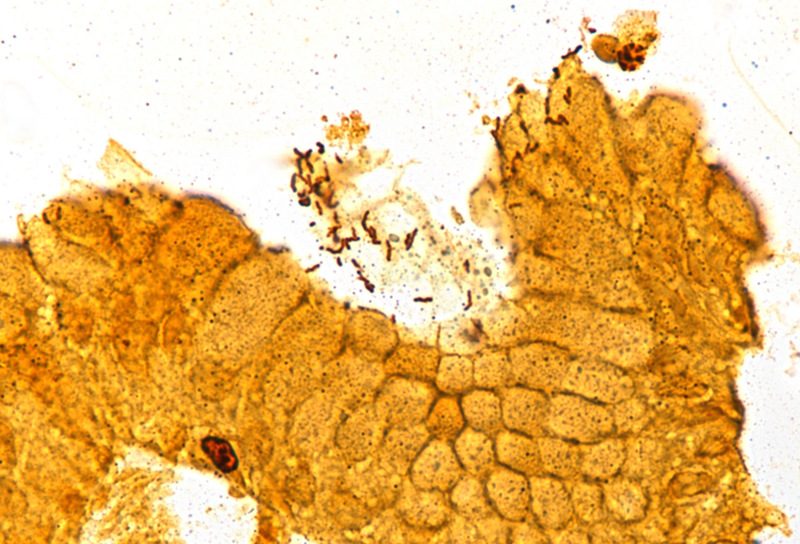

Microscopic examination revealed superficial chronic-active antrum and corpus gastritis (Panel A). In the mucus layer close to the surface epithelium, comma-shaped bacterial structures were detected and highlighted with a Warthin-Starry stain, consistent with Helicobacter pylori (Panel B). In the biopsies obtained from the corpus mucosa, a multifocal, predominantly lymphoplasmacytic infiltrate was seen in deeper parts of the mucosa. Specifically, the oxyntic glands were surrounded and infiltrated by lymphocytes (“emperipolesis”) resulting in gland destruction and parietal cell apoptosis. Occasional eosinophils completed the picture (Panels C-E). No significant atrophy and no metaplastic changes were observed.